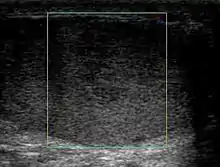

However, these patterns, except the latter one, may be considered as non-specific as heterogeneous echotexture and shadowing calcification can also be detected in malignant testicular tumors. The onion peel pattern of epidermoid cyst [Fig. 10] correlates well with the pathologic finding of multiple layers of keratin debris produced by the lining of the epidermoid cyst. This sonographic appearance should be considered characteristic of an epidermoid cyst and corresponds to the natural evolution of the cyst. Absence of vascular flow is another important feature that is helpful in differentiation of epidermoid cyst from other solid intratesticular lesions.